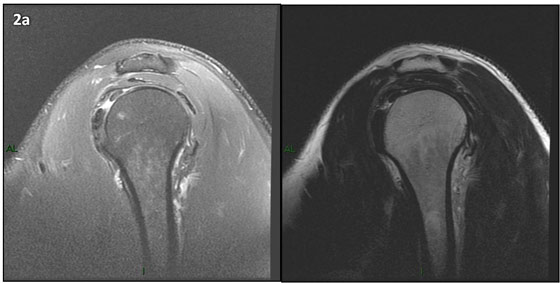

Figura 2 (a-j): Imagens consecutivas de RM no plano sagital nas ponderações T2 com supressão de gordura (DP SG) à esquerda e T2 à direita. Clique na seta para passar as imagens.

Figura 2 (a-j)': Imagens consecutivas de RM no plano sagital nas ponderaçõesT2 com supressão de gordura (DP SG) à esquerda e T2 à direita. Clique na seta para passar as imagens.

Figura 2a’ mostrando os tendões do subescapular (seta rosa), da cabeça longa do bíceps (seta verde), do supraespinhal (seta vermelha), do infraespinhal (seta laranja) e do redondo menor (seta amarela).

Figuras 2b a 2j’: Acompanhando o tendão do redondo menor (seta amarela fina) é possível notar lipossubstituição ao redor da junção miotendínea (setas amarelas grossas) e a atrofia principalmente da porção mais lateral (seta salmão). A porção mais medial (seta branca) tem volume preservado.

Repare que estas alterações também não são evidentes nas imagens com supressão de gordura no plano sagital.